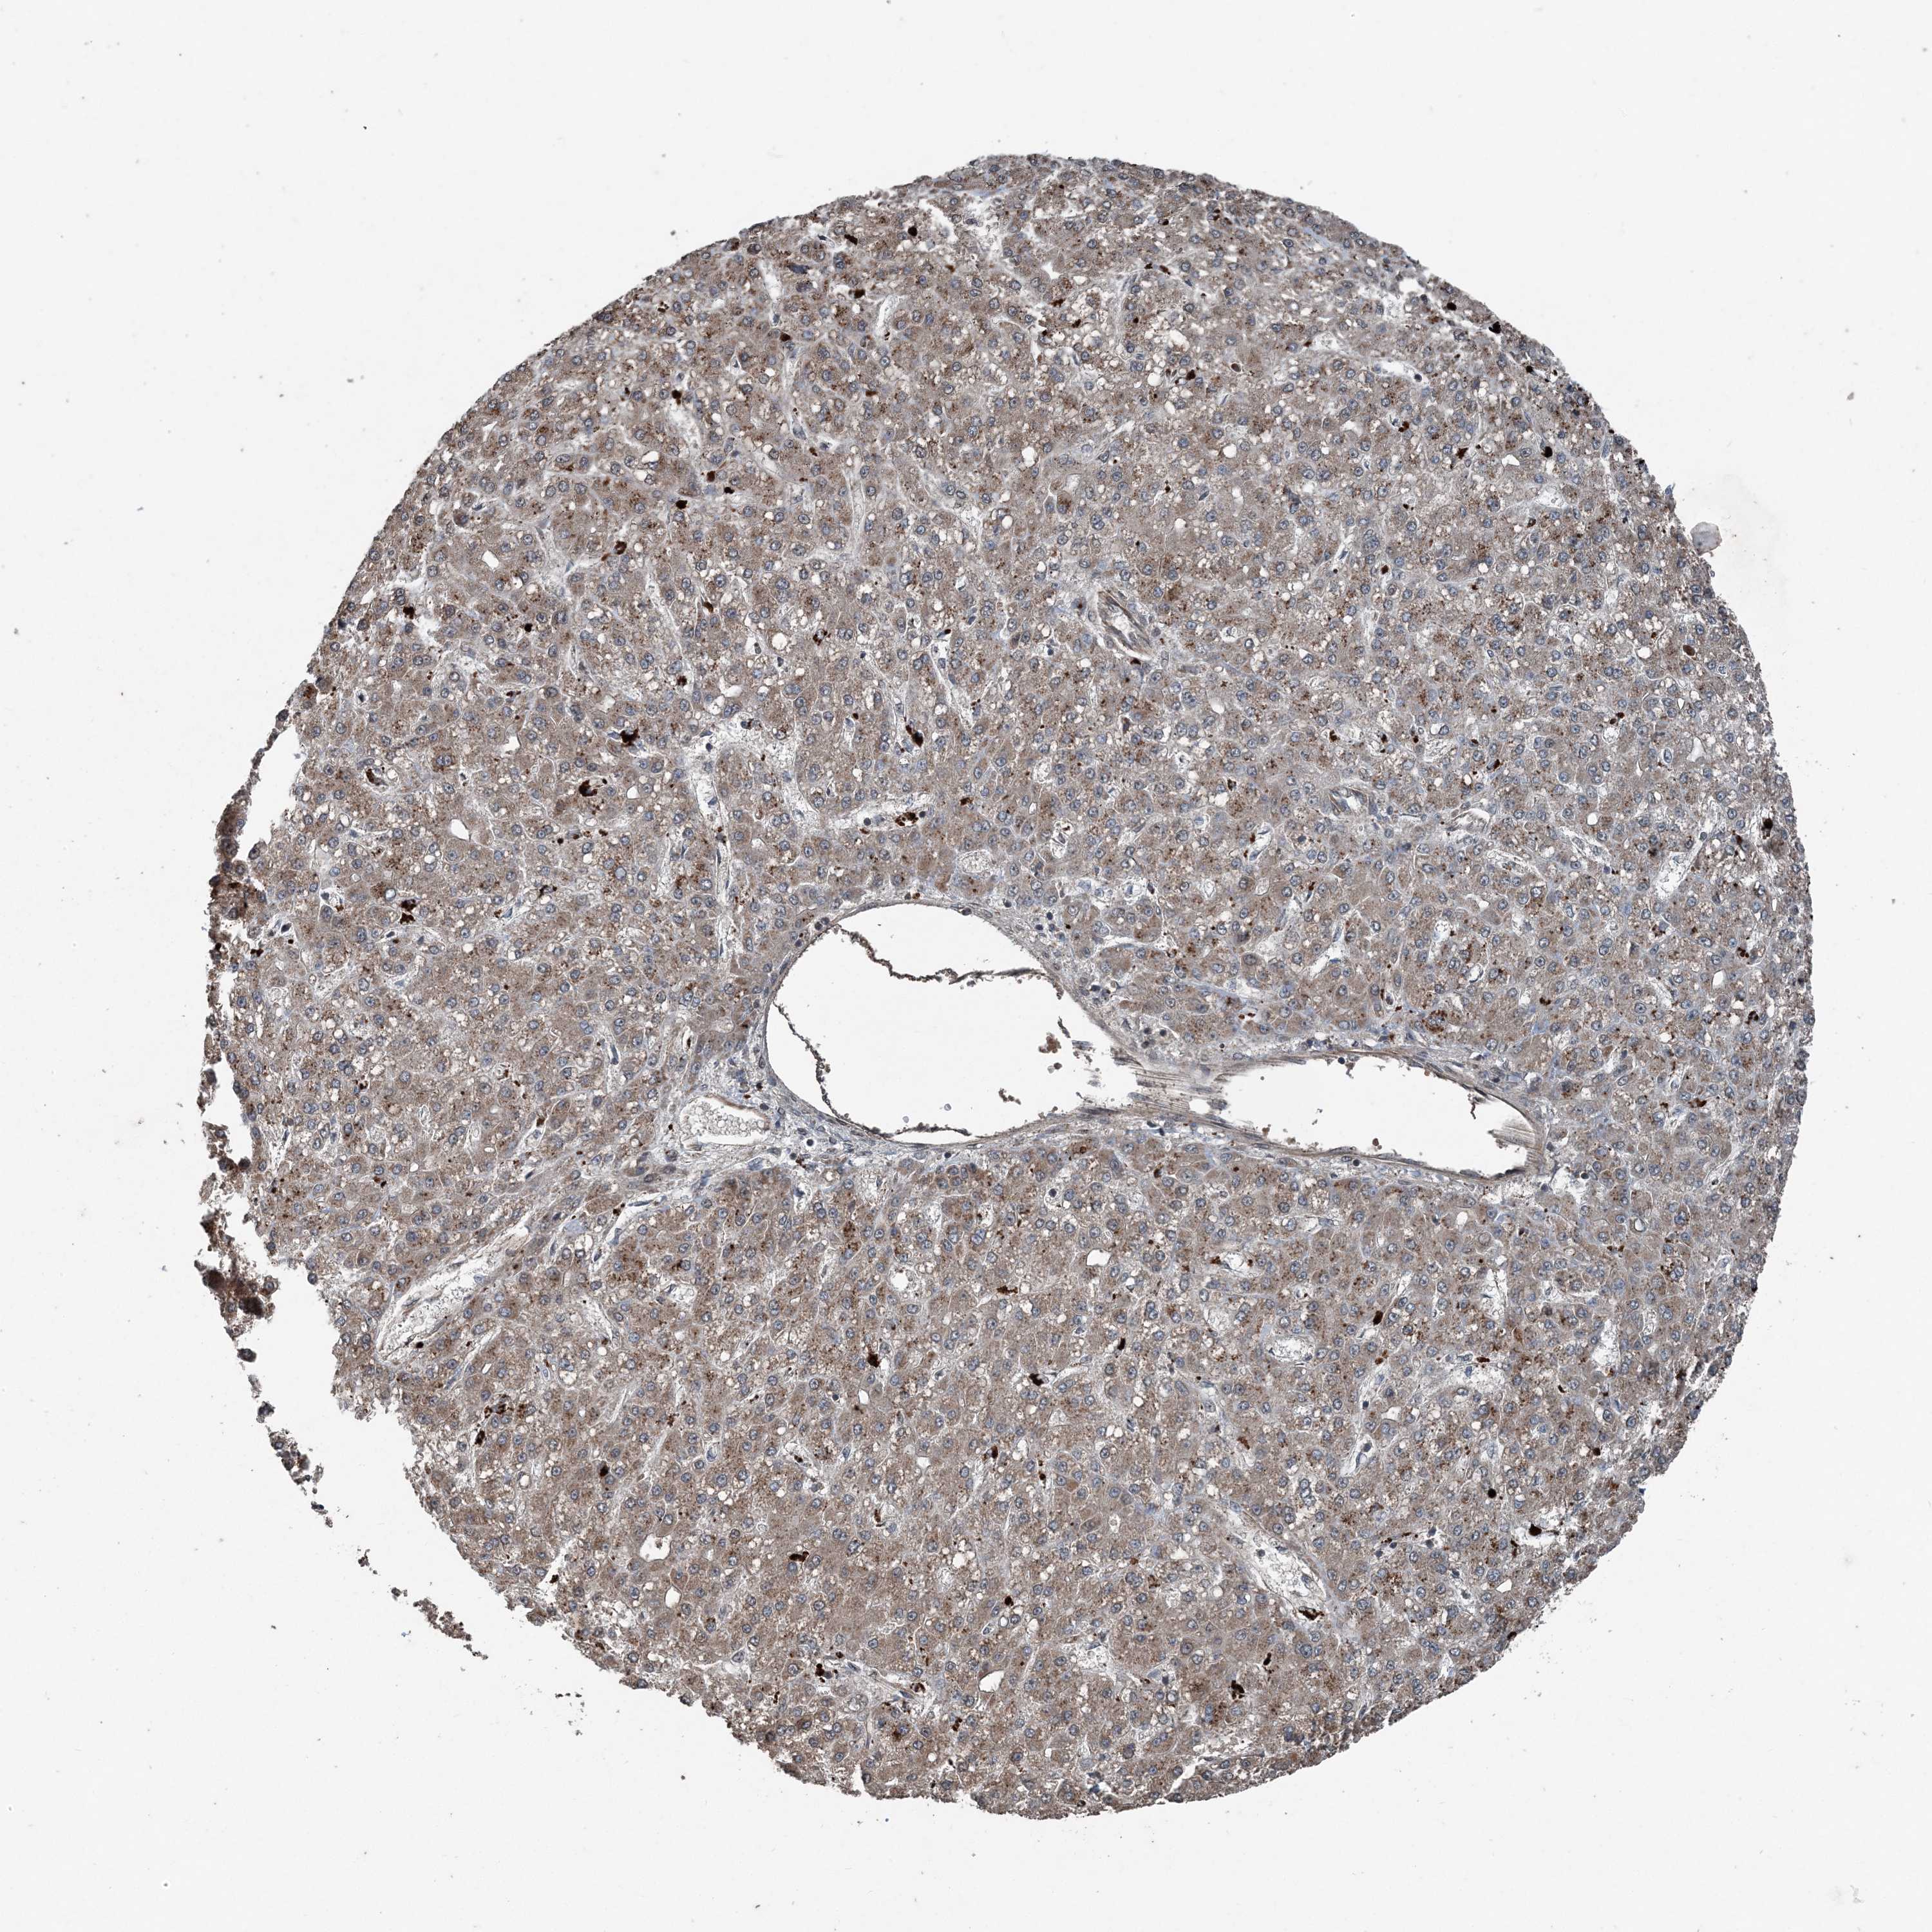

LIVER CANCER - Protein expressioni

A mouse-over function shows sample information and annotation data. Click on an image to view it in a full screen mode. Samples can be filtered based on level of antibody staining by selecting one or several of the following categories: high, medium, low and not detected. The assay and annotation is described here.

Note that samples used for immunohistochemistry by the Human Protein Atlas do not correspond to samples in the TCGA dataset.

Antibody stainingi

Antibody staining in the annotated cell types in the current human tissue is reported as not detected, low, medium, or high, based on conventional immunohistochemistry profiling in selected tissues. This score is based on the combination of the staining intensity and fraction of stained cells.

Each image is clickable and will lead to virtual microscopy that enables deeper exploration of all samples and also displays staining intensity scores, fraction scores and subcellular localization as well as patient and tissue information for each sample.

Antibody HPA053761

Cholangiocarcinoma

Carcinoma, Hepatocellular, NOS